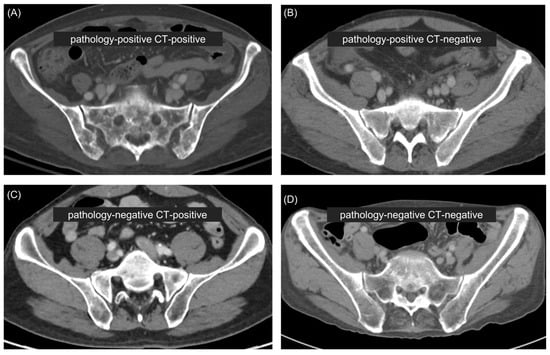

2.3. Assessment of APCT Images

3.2.1. In the Entire Patient Population

3.2.2. In the Pathology-Positive CT-Negative Group

3.2.3. In the External Validation Cohort